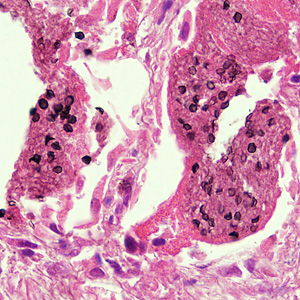

P. jirovecii has a special predilection for lung tissues. It attaches to the Type I alveolar epithelium, which allows the fungus to transition from its small trophic form to the larger cystic form. It causes hypertrophy of alveolar cells. The inflammatory response of the host causes lung injury and may also result in infiltration of macrophages; filling alveolar spaces with foamy eosinophilic material and plasma cells. This impairs gaseous exchange, leading to hypoxia and possibly respiratory failure.

Giemsa stain is used to demonstrate the nuclei of trophozoites and intracystic stages and silver stain is used to demonstrate the cyst wall. Immunofluorescence microscopy using monoclonal antibodies can detect both cystic and trophic forms with higher sensitivity than conventional microscopy.